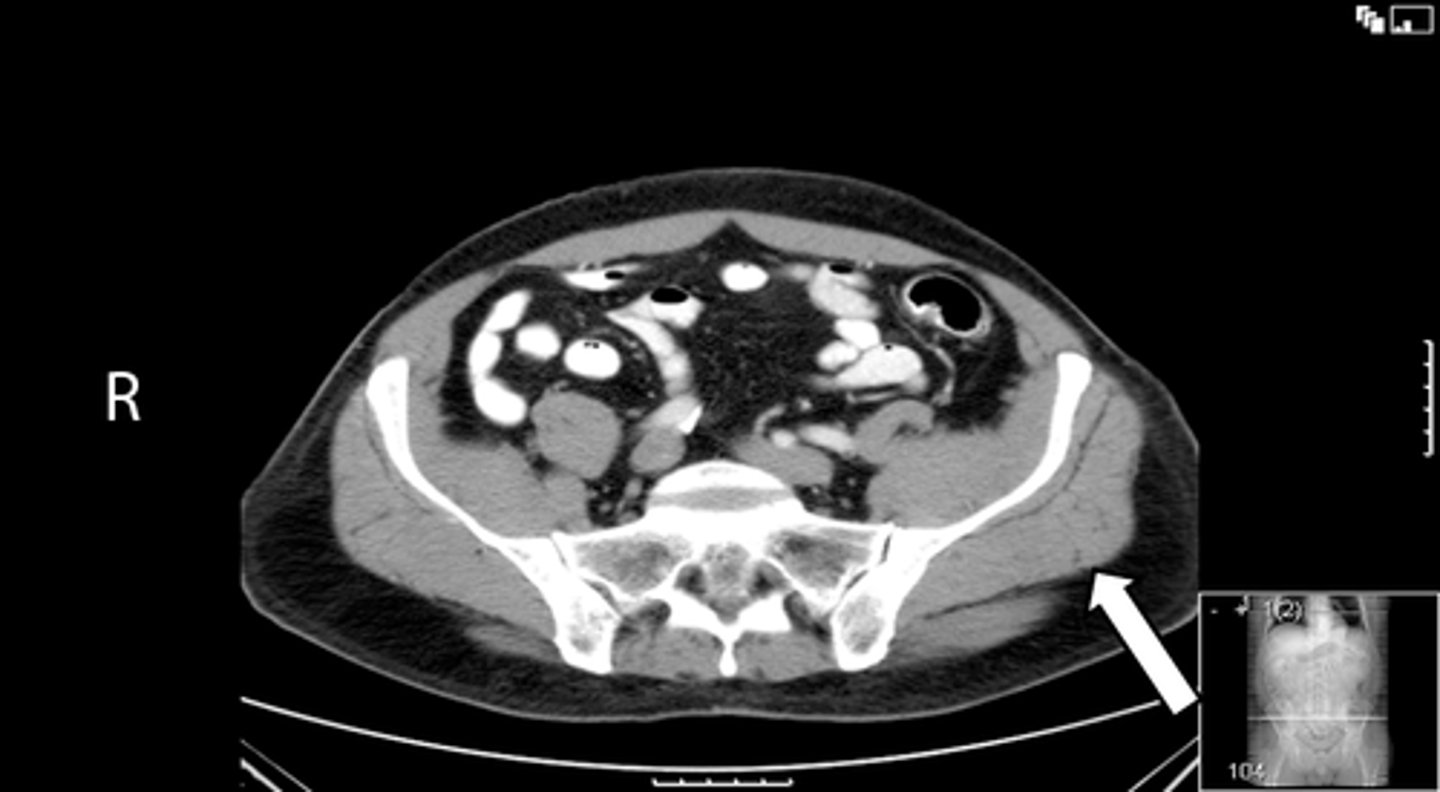

Axial bony pelvis CT

What is the image?

38

L acetabulum

<p>What is indicated in the image?</p>

New cards

What is indicated in the image?

40

L piriformis muscle

42

R piriformis muscle

44

Sacrum